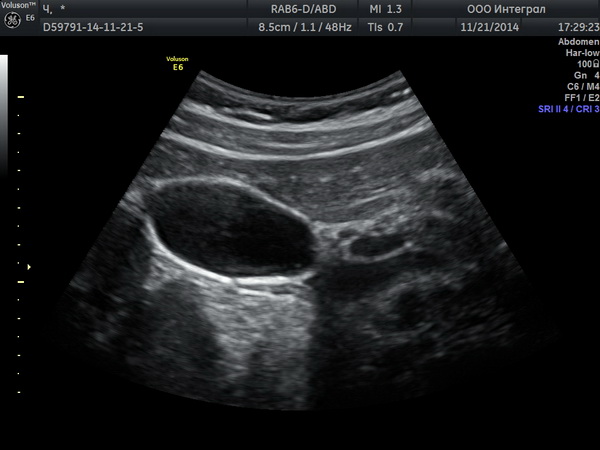

Врач предупреждает, что если у вас имеются подобные проявления, обратитесь к гастроэнтерологу, сделайте УЗИ. Вовремя выявленный застой желчи и его лечение, избавляет от многих проблем.